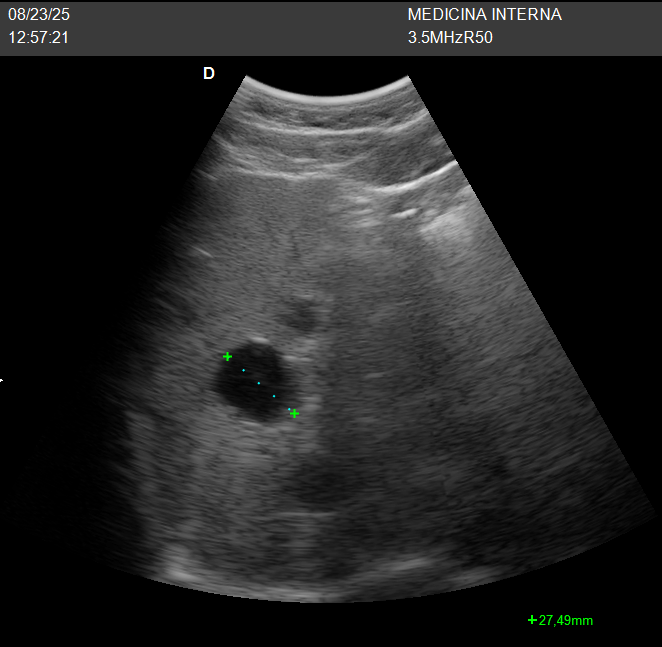

Aspecto en ecografía

- Anecoico (negro), redondeado/ovalado.

- Pared fina, márgenes bien definidos.

- Sin ecos internos, sin septos, sin nódulos murales.

- Refuerzo acústico posterior (aumento de brillo detrás del quiste).

Aspecto típico: lesión anecoica, bordes finos y refuerzo acústico posterior.

El caso en consulta

Paciente en seguimiento al que se detectó un quiste hepático simple hace años. En control ecográfico reciente, la lesión permanece estable, sin complicaciones ni síntomas. No se requiere tratamiento; solo observación clínica y control si cambian los síntomas.